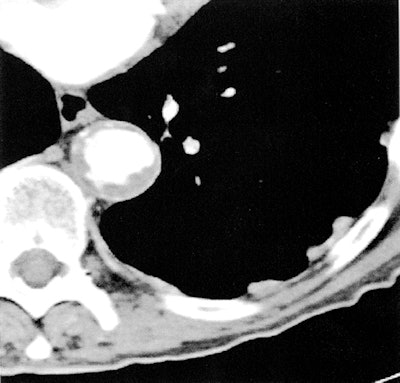

![]() |

| Aortic findings on transverse CT image shows irregular descending aorta with plaques and some calcified foci. Image republished with permission of the Radiological Society of North America from Radiology, November 2010, doi: 10.1148/radiol.10100054. |